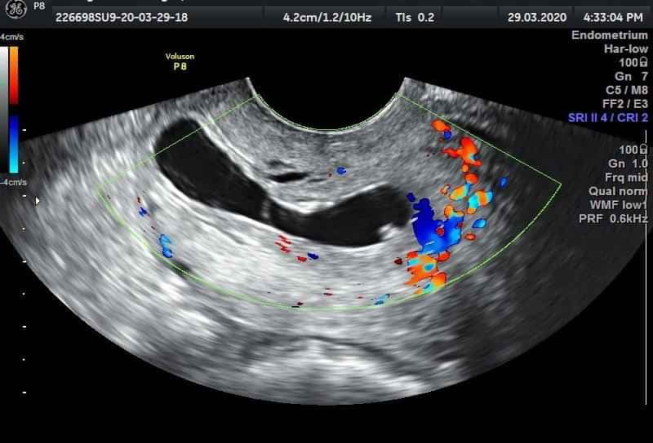

Bệnh nhân L.T.N.H 42 tuổi, PARA (2092) 2 lần sinh thường, 9 lần sẩy thai có nhiều lần can thiệp buồng tử cung, trể kinh, thử thai dương tính đi khám tại phòng khám tư nhân với chẩn đoán thai làm tổ ống cổ tử cung, bệnh nhân được nhập viện cùng ngày, lâm sàng trể kinh 2 tuần, không đau bụng, không ra máu âm đạo, đặt mỏ vịt thấy cổ tử cung lớn, mạch máu tăng sinh nhiều, nổi rõ mạch lên tại vùng cổ tử cung, cổ tử cung hở lỗ ngoài, siêu âm thai 6 tuần tại vị trí cổ tử cung, tim thai dương tính, phổ Doppler thấy tăng sinh mạch mạnh tại vùng cổ tử cung và có tính hiệu Doppler màu tại bánh nhau.Bệnh nhân được làm xét nghiệm công thức máu, chức năng gan, thận và chức năng đông máu trong giới hạn bình thường. Bệnh nhân theo dõi tại viện sau 3 ngày (vào viện chiều thứ 6) và hội chẩn khoa tại phòng siêu âm: chẩn đoán thai 6 tuần 3 ngày làm tổ tại cổ tử cung, tim thai dương tính. Xét nghiệm beta hCG 78352 mIU/ml, được chỉ định điều trị tiêm MXT tại chổ và hóa trị liệu toàn thân bằng MTX: Tiến hành hút hết ối, tiêm MTX tại khối thai 25 mg, tại bánh nhau 25 mg, sau 2 tiếng kiểm tra tim thai âm tính tiêm bắp MTX25 mg (tổng liều 75mg). Sau 3 ngày bệnh nhân xuất hiện đau bụng vùng dưới, tiến hành nạo gắp khối thai chủ động bằng kẹp đầu vợt, máu tại cổ tử cung ra nhiều, dùng sonde foley số 16 bơm từ từ lên 50 ml nước thì cầm được máu, lưu sonde, theo dõisau 20 phút bóng tuột, tiến hành đặt lại bóng với 50 ml nước muối, sau đó chèn gạc kín âm đạo, sau 24 giờ rút sonde, không còn ra máu. Kết quả xét nghiệm lại β-hCG 4626 mIU/ml. Bệnh nhân được cho ra viện sau đó 2 ngày. Sau một tuần xét nghiệm β-hCG 343.18 mIU/ml, sau 5 tuần β-hCG 2.42 mIU/ml. siêu âm tử cung phần phụ chưa phát hiện bất thường.

Hình 2.Hình ảnh siêu âm đường bụng sau hút ối tiêm methotrexate tại bánh nhau và túi thai

Ở những bệnh nhân ổn định huyết động, siêu âm không cho thấy hoạt động của tim thai và thai kỳ dưới 9 tuần, có thể dùng MTX toàn thân [10]. Thai kỳ hơn 9 tuần hoặc có sự hiện diện của hoạt động tim thai trên bệnh nhân ổn định về mặt lâm sàng có thể tiêm kali clorua/ MTX trong nước ối ngoài MTX toàn thân [10]. Chẩn đoán tại thời điểm tam cá nguyệt thứ 2 hoặc thứ 3 có thể cắt tử cung.Ở bệnh nhân xuất huyết, các lựa chọn điều trị là chèn ép bằng bóng Foley, thắt mạch lớn hoặc thuyên tắc mạch, cắt bỏ tử cung dành cho những trường hợp chảy máu khó cầm [10]. Thông thường, nhiều hơn một phương pháp thường được thử để điều trị thai OCTC [10]. Do đó, trong trường hợp của chúng tôi, chúng tôi chọn điều trị bệnh nhân bằng tiêm MTX tại buồng ối vì tim thai còn hoạt động, tiêm MTX tại bánh nhau, sau khi siêu âm tim thai âm tính thì tiêm MTX toàn thân, tổng liều 75 mg như liều điều trị của thai làm tổ tại vết mổ cũ [12]. Thai OCTC là một bệnh ít gặp nên bằng chứng về việc sử dụng MTX để điều trị thai OCTC được giới hạn trong các báo cáo ca bệnh và loạt nhỏ, các liệu pháp khác nhau đã được sử dụng (MTX toàn thân đơn hoặc đa liều, tiêm MTX hoặc KCl tại chỗ, hoặc kết hợp các liệu pháp này).Dữ liệu trước đó cho thấy kết quả không khả quan nếu beta hCG huyết thanh hơn 10,000 mIU / ml [13]. Tuy nhiên, trong báo cáo gần đây của Samal và cộng sự, một ca chửa ngoài cổ tử cung cho thấy thai nhi sống được 7 tuần 4 ngày với beta hCG là 103,113 mIU / ml đã được điều trị thành công bằng đa liều MTX và KCl trong buồng ối, sau đó hút ống cổ tử cung [14]. Một mũi tiêm MTX cục bộ tại túi thai, có hướng dẫn bằng siêu âm, rõ ràng có hiệu quả để điều trị thai OCTC mà không cần các thủ thuật đồng thời hoặc can thiệp phẫu thuật [15]. Sau khi có hiện tượng sẩy thaichúng tôi chọn lựa gắp khối thai bằng panh và chèn ép cổ tử cung bằng sonde Foley khi có chảy máu vì đây là phương pháp chủ động và ít xâm lấn nhất. Sau đó thẽo dõi có hiện tượng chảy máu do tuột bóng chúng tôi tiến hành đặt lại bóng và dùng gạc chèn kín âm đạo để giữ bóng trong ống cổ tử cung.